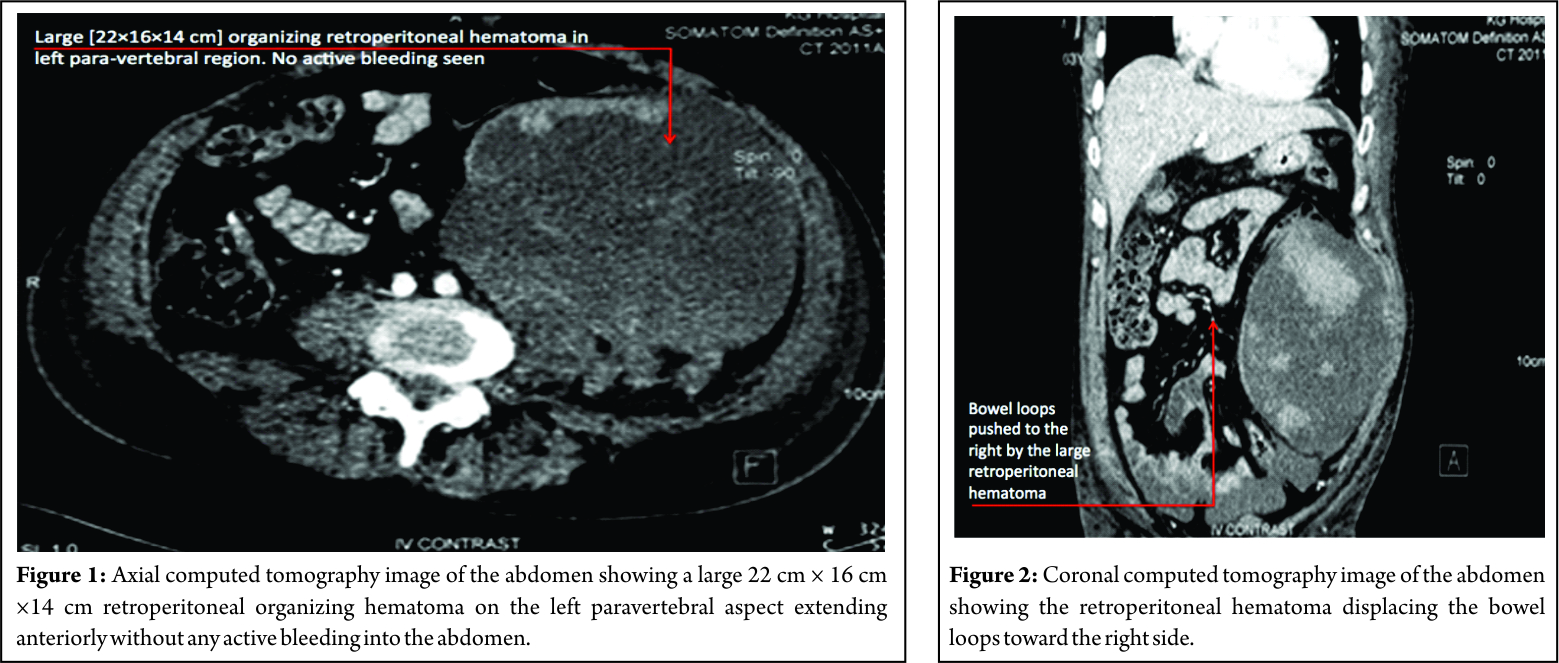

On clinical examination, he had a distended abdomen, pitting edema over the left lumbar region and left thigh, with weak (Grade 2) quadriceps along with reduced sensations over the anterior thigh. His knee reflex was absent on the left side, and hip and knee movements were painful. Left femoral pulse was feeble, and the patient was unable to perform a straight leg raise. Movements of opposite hip and knee were full and pain-free with an intact neurovascular status. Investigations had revealed that the total counts, renal parameters, and liver enzymes were elevated with a hemoglobin of 8 g/dl. Ultrasound abdomen revealed a large mass in the left hypochondrium and iliac region which was confirmed as a retroperitoneal organizing hematoma contiguous with the left psoas and iliacus without any active bleeding in the abdomen. The massive dimensions of the lesion were 22 cm × 16 cm × 14 cm (Fig. 1 and 2). The case was managed conservatively with cessation of anticoagulants, limb elevation and bed rest and had made complete neurological recovery at subsequent follow-up at 1 month.